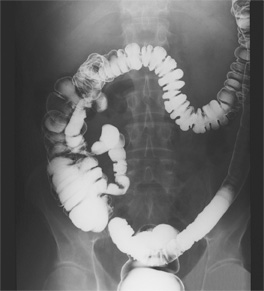

The exam is an X-ray that is taken of your colon. You will be asked to wear a gown and lie down on the exam table. Before the X-ray is taken, the healthcare provider or radiology tech will put an enema tube into your rectum. Liquid barium will be sent through this tube into your colon. You may feel that you need to have a bowel movement. You may also feel pressure or cramping in your stomach.

A fluoroscope machine lets the radiologist see the barium as it flows into your colon. After the first set of X-rays is done, you will be asked to go to the bathroom to get rid of the barium. Then more X-rays will be taken of your empty colon. As the X-rays are being taken, the radiologist will ask you to move into different positions. They may also press down on your stomach.